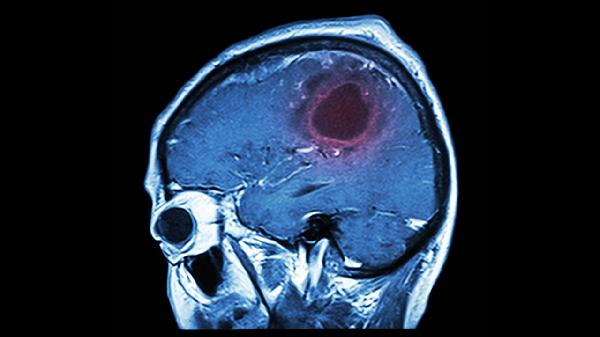

看到保温杯里飘着的几颗红枣枸杞,很多人第一反应是"养生标配",但谁能想到这杯看似温和的饮品背后藏着健康隐患?一位68岁的阿姨因为长期过量饮用这类滋补汤水,最终导致脑血管意外,家人后悔莫及。其实生活中类似的养生误区比比皆是,那些被我们奉为"神仙水"的日常饮品,可能正在悄悄伤害身体。

中医讲究"辨证施治",但很多人把养生汤当成万能药。体质偏热的人频繁饮用温补类汤水,相当于火上浇油。那位住院的阿姨就是典型例子,本就有高血压还每天三碗红枣汤。